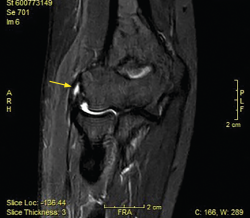

Figura 12. Imágenes de resonancia magnética de un codo izquierdo. Se aprecia una plica posterolateral de codo en el plano coronal (A) y en el plano sagital (B y C).

La RM permite visualizar un tejido similar a un menisco en la cara lateral de la articulación radiocapitelar que se interpone entre la cabeza radial y el capitellum (Figura 12). Las plicas pueden localizarse en el lado anterolateral, en el posterolateral o en ambos, siendo más frecuente la localización posterolateral. La RM nos permite medir su grosor, así como su longitud. El grosor medio de las plicas patológicas suele estar en torno a 3,7 ± 1,0 mm, que es significativamente más grueso que el valor de una plica normal (1,8 ± 1,4 mm)(6). La longitud del pliegue medida en coronal y sagital (9,4 ± 1,6 y 8,2 ± 1,7 mm, respectivamente) también es mayor que los valores normales (3,9 ± 1,5 y 4,3 ± 1,5 mm)(35). Se debe tener en cuenta que no todas las plicas son patológicas ni sintomáticas, independientemente de su tamaño. Es necesario apreciar edema en el tejido que conforma la plica o a su alrededor y tener una clínica compatible. La artrorresonancia puede ser de utilidad en caso de dudas.